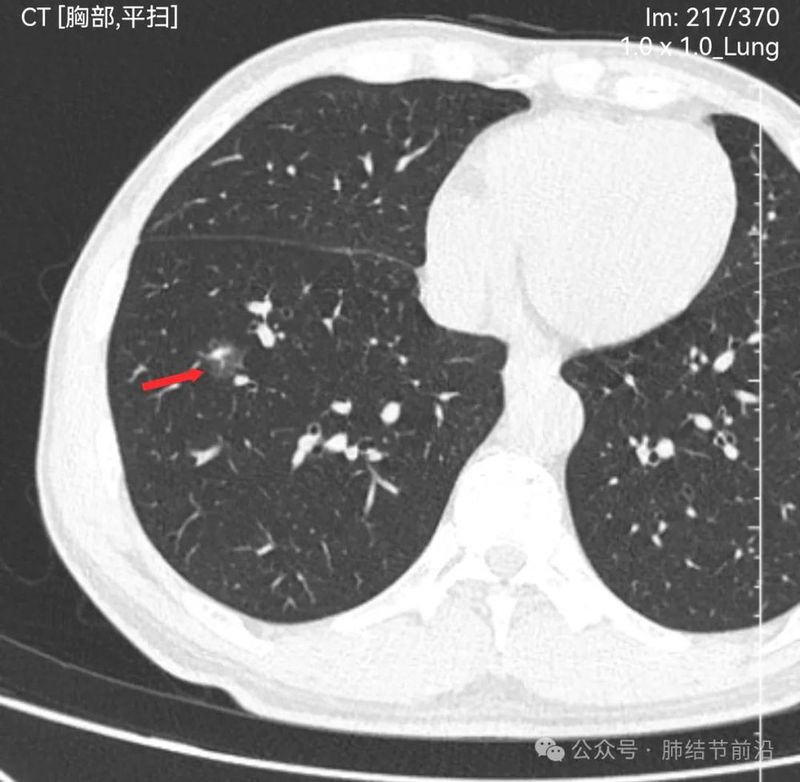

见右下肺纯磨玻璃结节14mm。有“血管穿过”、空泡。磨玻璃边界清楚而不毛糙。形态上是典型的肿瘤性磨玻璃,以微浸润腺癌可能大。